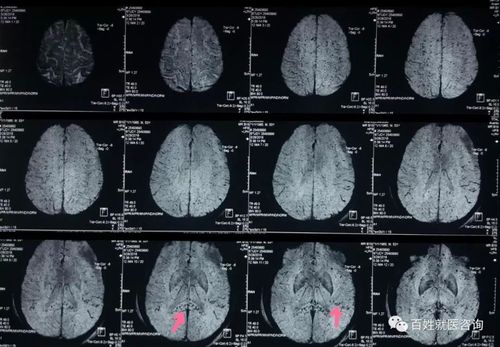

核磁共振片子 头部

核磁共振片子 头部,核磁共振片子头部

头部核磁共振检查大脑半球散在腔灶或脑蛋白脱髓鞘病变

如下图所示: 上图磁共振片,弥漫点状低信号出血点,就是剪切